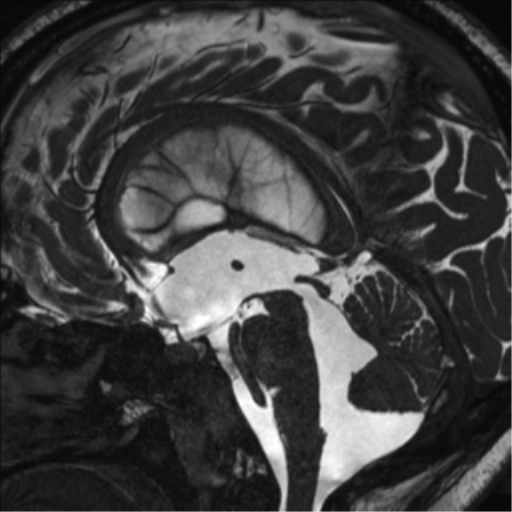

Giảm áp lực nội sọ (Spontaneous intracranial hypotension - SIH)

• Giảm áp lực nội sọ (Spontaneous intracranial hypotension - SIH)